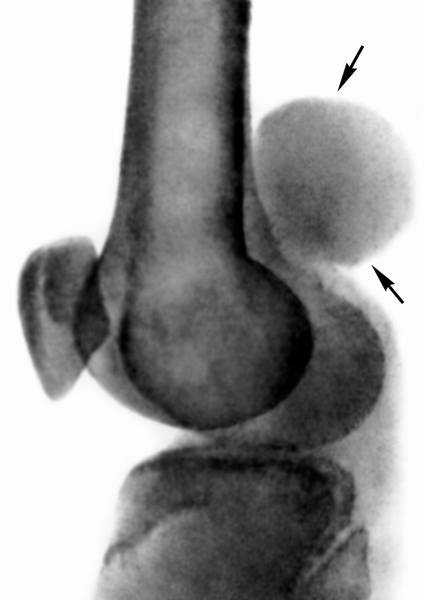

Рентгенологическое исследование и компьютерная томография выявляют признаки опухолевидного образования, часто с участками кальциноза, расположенными в его центральной части. В большинстве случаев отмечаются деструктивные изменения прилежащей кости различной степени выраженности. При ангиографии пораженного участка в области синовиомы наблюдается патологическое разрастание сосудов.